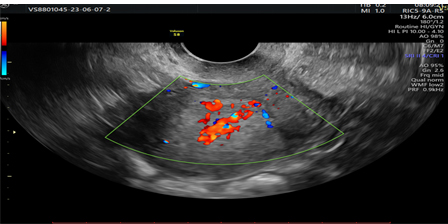

Vascular pattern: single blood vessel with or without laceration, multiple blood vessels of focal origin, multiple blood vessels of multifocal origin, scattered blood vessels(Pictures 1-6).

Picture 5.Prominent Doppler flow diagram.